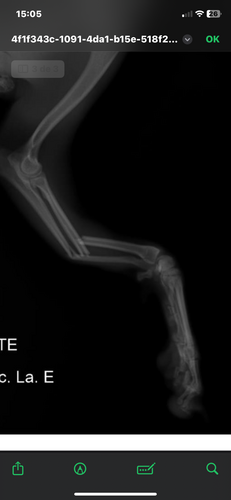

Oi, pessoal! Meu nome é Helen e esse é o Chico, meu pinscher cheio de energia, carinho e amor. Ele é parte da família, sempre alegre e protetor, mas infelizmente sofreu um acidente e fraturou o bracinho (membro torácico esquerdo).

Levamos o Chico ao veterinário e, após os exames e radiografias, o diagnóstico foi uma fratura deslocada que precisa de cirurgia com placa e parafusos. O procedimento é essencial para que ele volte a andar e brincar sem dor.